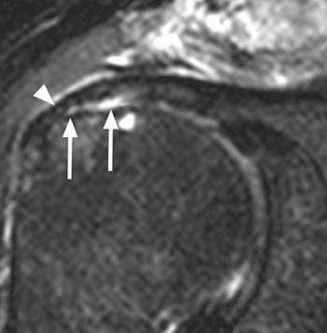

Figure 2–8_Reproduced with permission from Stadnick ME. _Partial Rotator Cuff Tears. MRI Web Clinic. 2007 (Apr).

The correct answer is (A). These are best diagnosed on an MRI as seen in the imaging provided; addition of intra-articular contrast can further improve this study. Answer B, full-thickness rotator cuff tear, is incorrect as the bursal side of the tendon can be seen to be in continuity. Answer C, a SLAP lesion, will be visualized as a labral tear on a coronal MRI and will be found at the biceps root. Answer D, an ALPSA lesion, will be most clearly seen on an axial MRI. It is a variant of a Bankart lesion where the labrum is displaced medially and inferiorly rolling down the glenoid neck underneath the periosteum.

MRI remains the most popular imaging modality for diagnosing rotator cuff tears. Normal rotator cuff tendon appears dark on both T1 and T2 sequences. Tears may be noted as being full-thickness, articular-sided, bursal-sided, or intrasubstance. They are visualized as a disruption in the regular contour of the tendon and increased signal intensity on T2 sequences. Occasionally, an MR arthrogram may provide additional information regarding a cuff tear, although this is not routinely ordered.